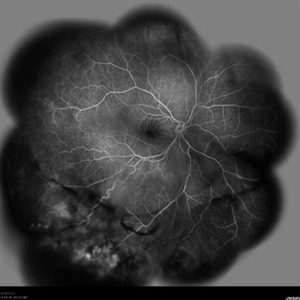

Behcet's Disease Behcet's DiseaseMar 13 2013 by Hamid Ahmadieh, MD Wide field FA of the right eye of a 23-year-old man with retinal vasculitis and branch retinal vein occlusion (BRVO) due to Behcet's disease . Photographer: Solmaz Shahmohammad, Negah Eye Center, Tehran Imaging device: Heidelberg Spectralis Condition/keywords: branch retinal vein occlusion (BRVO), retinal vasculitis